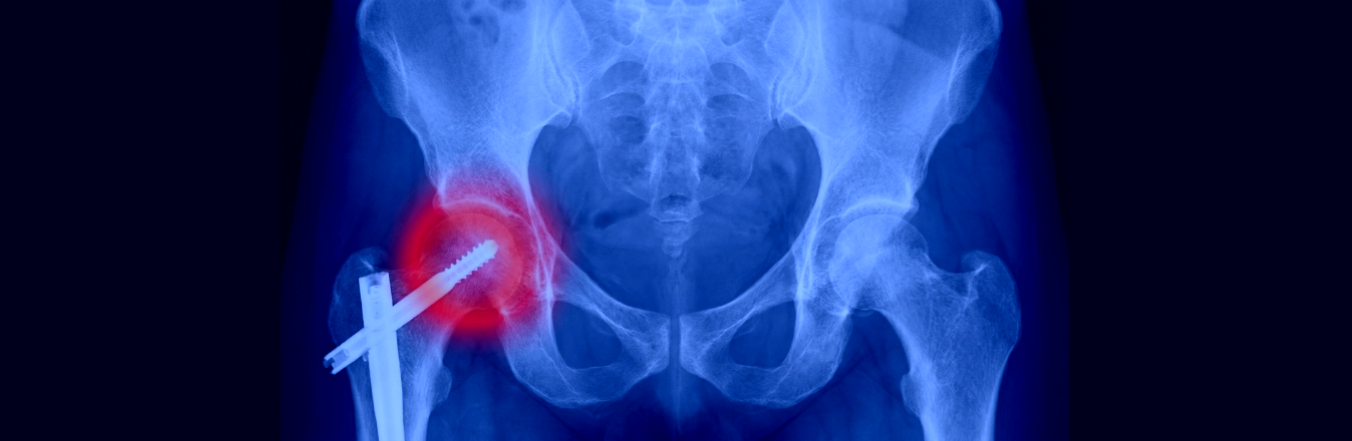

Dopo una frattura del collo del femore, una lussazione o qualsiasi altro trauma che coinvolge l’anca, così come dopo un intervento chirurgico come una protesi d’anca, possono insorgere complicanze o problematiche residue che limitano la mobilità e causano dolore persistente.

• radiografie per valutare la consolidazione ossea, la posizione degli impianti e l’usura.